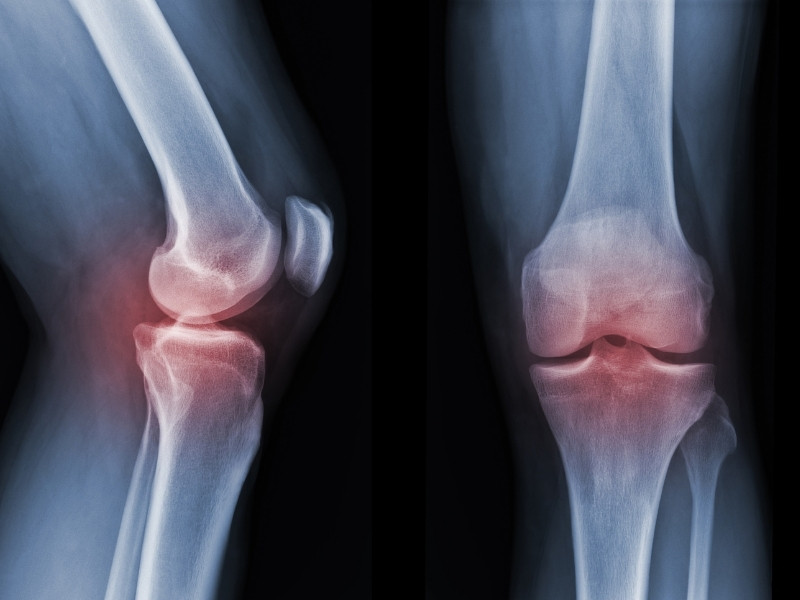

Diz Kireçlenmesi nedir?

Diz eklemini örten kıkırdak dokunun zamanla aşınması ve incelmesi sonucu oluşan bir hastalıktır. Genellikle yaşla birlikte artış gösterse de gençlerde de görülebilir.